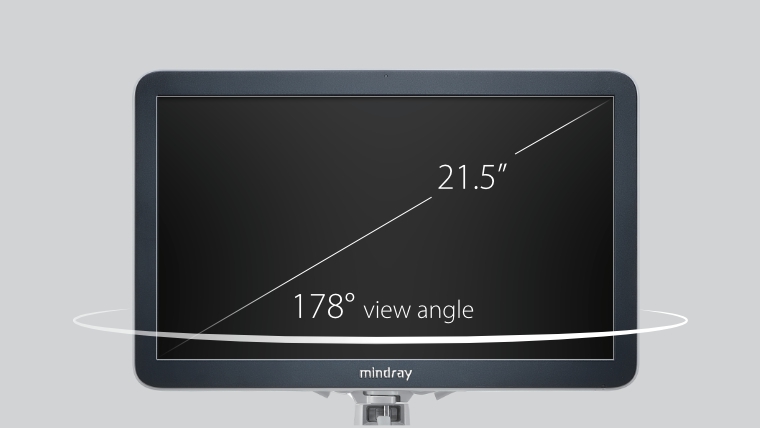

21,5-Zoll-Monitor im Full-HD